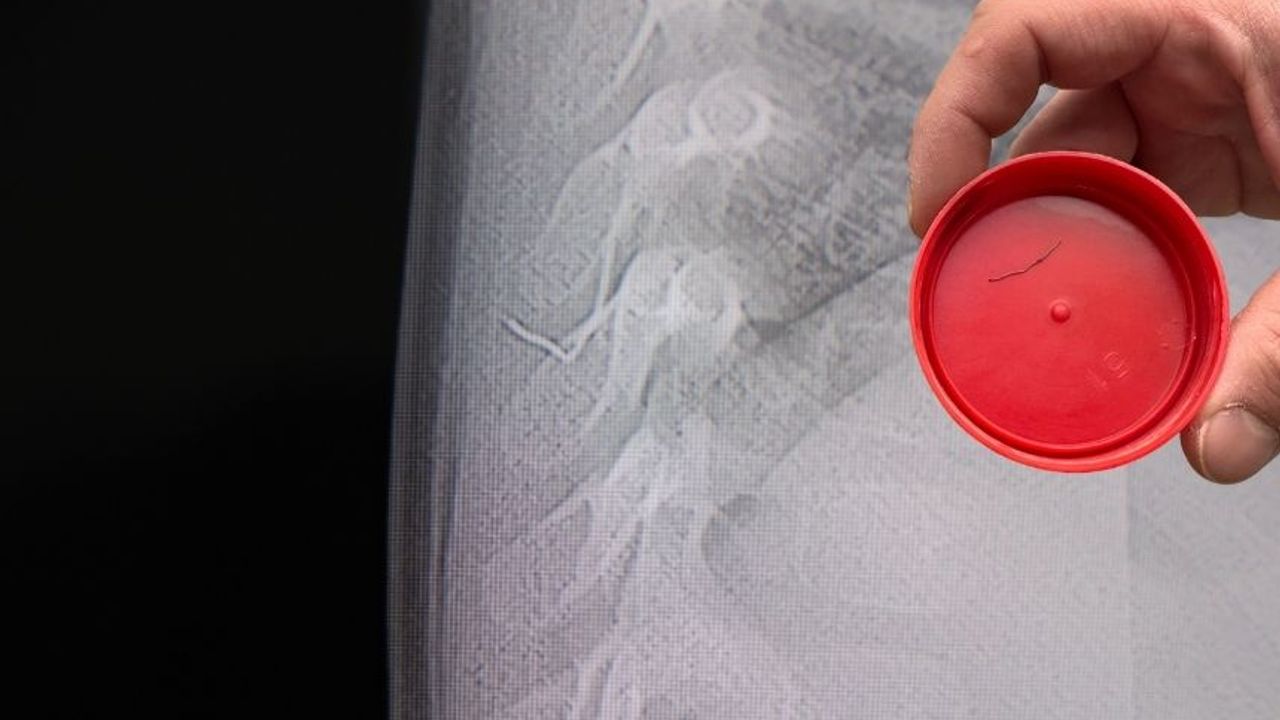

Alınan bilgiye göre, Kahramanmaraş'ta farklı ortopedi, çocuk cerrahisi ve beyin cerrahisi kliniklerine başvurusu yapılan bir yaşındaki bebeğin, sırt bölgesinde yabancı bir cisim olduğu ancak müdahalenin zor olduğu ve 8 yaşına kadar beklenmesi gerektiği bildirildi. Aile, bebekleri için son olarak HG Hospital'e başvurdu. HG Hospital Beyin ve Sinir Cerrahisi Uzmanı Prof. Dr. İdris Altun tarafından yapılan tetkiklerde, yabancı cismin cilt altında, omurilik kanalına yakın bir bölgede olduğu ve akciğer zarına doğru ilerlediği belirlendi. Hasta, genel anesteziye alınmadan, lokal anestezi ve sedasyon eşliğinde ameliyata alındı. Yapılan müdahalede yabancı cisim tamamen çıkarıldı. Çıkarılan cismin, ince zımba teline benzer metal bir tel olduğu ve yaklaşık 2 santimetre uzunluğunda bulunduğu tespit edildi. Hasta, aynı gün taburcu edildi.

Konuya ilişkin açıklama yapan Prof. Dr. İdris Altun, "Sırtında yabancı bir cisim olduğu söylenmiş ancak çıkarılamayacağı ve 8 yaşına kadar beklenmesi gerektiği ifade edilmişti. Bize başvurduğunda yaptığımız tetkiklerde, cilt altında, omurilik kanalına çok yakın ve akciğer zarına doğru ilerleyen bir yabancı cisim tespit ettik. Hastamızı tamamen uyutmadan, lokal anestezi ve sedasyon eşliğinde müdahale ederek lezyonu tamamen çıkardık. Çıkardığımız cismin ince zımba teline benzer, yaklaşık 2 santimetre uzunluğunda metal bir tel olduğunu gördük. Bu yabancı cisim alınmasaydı, bölgede enfeksiyon gelişebilirdi. Enfeksiyon sonucu omurilik kanalında ciddi hasarlar oluşabilir, çocuk büyüdükçe cismin hareket etmesine bağlı olarak omurilikte zedelenmeler meydana gelebilirdi. Ayrıca yana doğru ilerleyerek akciğer zarına ve akciğere batma riski vardı. Bu da enfeksiyona ve ilerleyen süreçte tümörle karışabilecek tablolara neden olabilirdi. Şu an hastamız gayet sağlıklı. Gerekli kontrolleri yaptık ve aynı gün taburcu ettik" dedi.